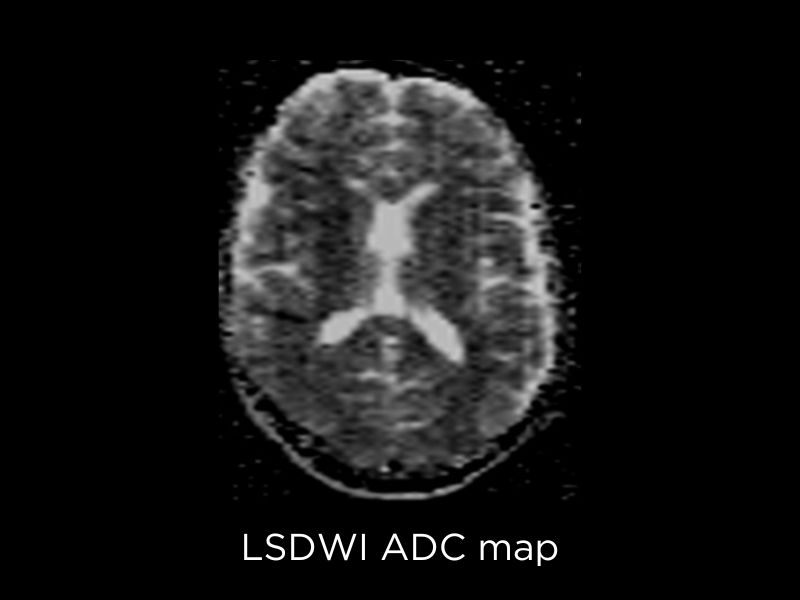

Neuroimaging clinical images

Diffusion Weighted Imaging (DWI) is a fundamental sequence to detect brain tumors, their classification and grading and monitoring. On Magnifico Open, Esaote implemented the DWI sequence with line scan technology1: this technique is based on spin echo sequences and has reduced susceptibility to static field inhomogeneities than echo planar imaging (EPI). In addition, it does not require enhanced gradient hardware and offers easy installation and reduced power consumption.

DWI provides important clinical value especially in the assessment of Cerebral Infarction and Stroke, Neoplasia, Emphysema, Toxic and Demyelinating pathologies.